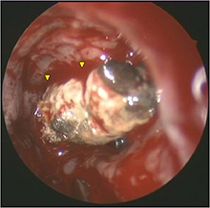

Aspergillom der linken Kieferhöhle (Endoskopisches Bild, 0°-Optik)